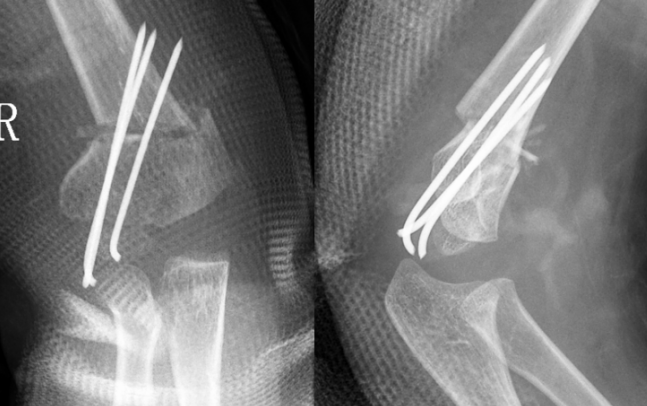

病例2:小红(化名)、女、9岁,3年前因摔伤致“左肱骨髁上骨折”,于当地诊所行手法复位夹板外固定,夹板固定一个月拆除外固定后逐渐发生左肘内翻畸形。

受伤当时的X线片

拆除夹板后的X线片

该例患者初始骨折为尺偏型肱骨髁上骨折,该种类型的骨折发生肘内翻畸形的可能性很大,需要在麻醉下手法复位纠正骨折端的尺偏移位,结合经皮克氏针固定,从而最大程度降低肘内翻畸形的发生率,但是当地诊所只是使用小夹板外固定,该固定不牢靠,骨折端容易再移位,且骨折端的尺偏移位纠正不足,种种原因引起了肘内翻畸形。针对该病例我们选择截骨矫形手术。

术后X线片示肘内翻矫正满意